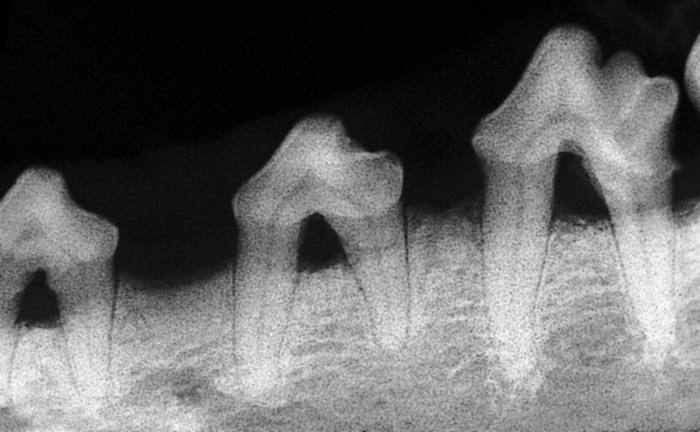

Stage 3: Moderate Attachment Loss

Probe indicates 6-7mm pocket

Radiograph showing up to 50% bone loss

Defined by attachment loss of 25% to 50% verified by probing and radiographs. Note that gingival recession occurring at the same time as deepening pockets may not increase the probing depths. However, attachment loss is still significant.